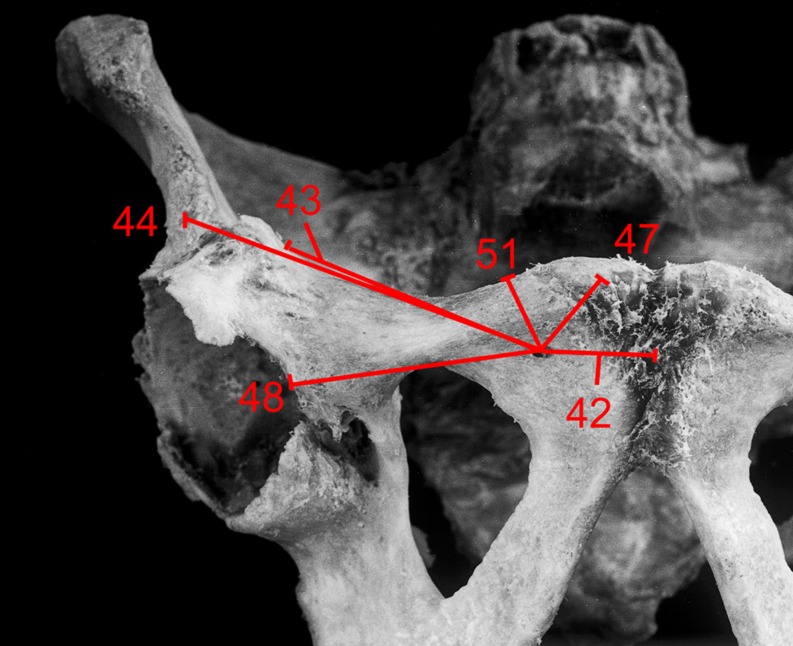

Fig. 2.

Specimen with retrograde entry point of anterior column screw. Distances to the different bony landmarks are marked in straight lines. Numbers are for identification use

At the entry point of the retrograde anterior column screw, there was a significant difference in the distance to the cranial rim of the superior pubic ramus (p = 0.002), with a shorter distance for female specimens (Table 1). The distance to the iliopectineal eminence, the anterior inferior iliac spine and the pubic tubercle showed low interspecimen deviation, with no distance exceeding 2.5 cm above the mean values.

Table 1.

Distance of screw entry point to various landmarks. Identification number in brackets (see Fig. 2)

| Distance of retrograde entry point anterior column screw to various landmarks | Male specimen | Female specimen | P value |

|---|---|---|---|

| Mean [cm; (range) standard deviation] | |||

| Centre of symphysis (42)a | 2.7 (2.0–3.1) 0.34 | 2.8 (1.4–4.2) 0.98 | 0.653 |

| Iliopectineal eminence (43)a | 5.4 (4.6–6.4) 0.60 | 5.3 (4.2–6.4) 0.82 | 0.749 |

| Anterior inferior iliac spine (44)a | 9.3 (8.5–9.8) 0.46 | 9.0 (8.1–10.0) 0.71 | 0.370 |

| Pubic tubercle (47)a | 1.7 (1.2–2.1) 0.28 | 1.4 (0.3–2.4) 0.70 | 0.368 |

| Medial acetabular rim (48)a | 5.0 (3.5–6.0) 0.88 | 4.8 (4.2–6.7) 0.98 | 0.847 |

| Cranial rim of superior pubic ramus (51)a | 1.5 (1.2–1.7) 0.20 | 0.9 (0.3–1.3) 0.38 | 0.002 |

asee Fig. 2